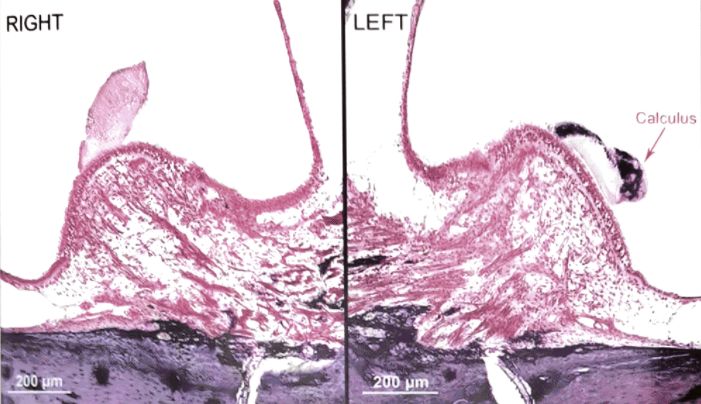

05 壶腹嵴和囊斑

Masutani等人发现,MD患者半规管嵴帽明显萎缩,毛细胞损伤丢失,暗细胞密度明显低于对照组,且形态异常。Kimura等人推断位于椭圆囊斑周围和半规管壶腹嵴的暗细胞,在前庭迷路电解质的主动转运中起重要作用,并与内淋巴的产生有关。因此,Masutani等报道的暗细胞异常似乎与MD患者的内淋巴水肿密切相关。而嵴帽的毛细胞丢失和萎缩则导致MD患者的温度试验呈不可逆性的轻瘫表现。

图12 壶腹嵴上皮明显萎缩

图13 后半规管暗细胞区。箭头表示肿胀的暗细胞,细胞核不明显

McCall等研究了MD患者的前庭神经上皮(壶腹嵴和椭圆囊)形态改变,发现92%的外半规管壶腹嵴、75%的球囊斑和24%的椭圆囊斑正常的上皮细胞结构被单层细胞部分或完全替代。其中,在大多数壶腹嵴中,存在严重的毛细胞丢失、基底膜增厚和纤维化。电镜下可见血管周围基底膜增厚,纤维细胞增多,壶腹嵴和椭圆囊斑内皮细胞胞浆空泡化(此基底膜并非耳蜗基底膜)。